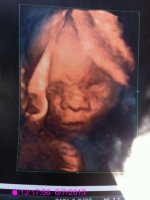

bebe automne hiver 2013

andrea06 a dit:Voilà je suis sorti, donc on a la confirmation que c'est un pti mec, zhom est trop content, elle nous a pas dit le poids ni la taille mais je serai tout à l'écho des 22sa le 18 juin !

Félicitations ! Elles sont top tes échos 3D!!

Trop cool que ton fils aille bien super qu'elle ta fait des écho 3D mais c'est quoi qu'il a autour de la tête moi snif mon Gyneco ne veut pas m'en faire tant qu'elle a des trucs autour d'elle lol

Elle la fait sans nous demander et ct vraiment bien parce qu'elle a fait une 4d en temps réel donc on voyait bb bouger en même temps, sinon je sais pas ce que c'est sur la tête !

Ah oui super on le voit bien en plus j'adore la 2 eme le penseur trop chouette lol sa doit être le cordon ou autre sûrement

jennyfouille a dit:Ah oui super on le voit bien en plus j'adore la 2 eme le penseur trop chouette lol sa doit être le cordon ou autre sûrement

Oui c'est la plus jolie, le cordon il l'avais bloqué entre ses jambes, et il a toujours la tête en haut !